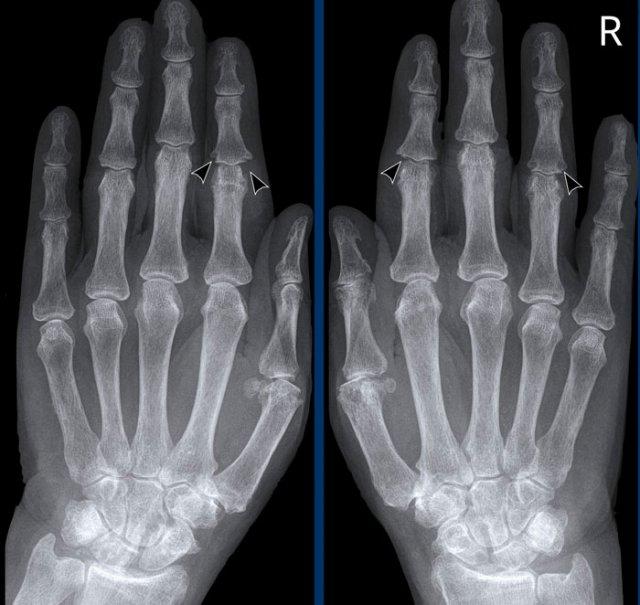

Hình ảnh bào mòn xương vùng rìa điển hình và hẹp khe khớp tại các khớp MCP 3-5.

Lưu ý hình ảnh hẹp khe khớp đồng đều tại các khớp MCP.

Các khớp liên đốt gần (PIP) chỉ biểu hiện hẹp khe khớp tối thiểu.